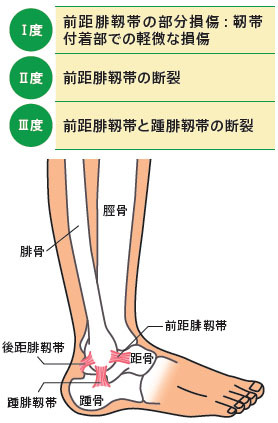

湿布の効果は何時間?短い時間でも効果はある?薬剤師が湿布 捻挫した場合にサポーターはいつまで着ける?その期間とは!? 足関節(足首)捻挫には湿布?アイシング?テーピング?捻挫 捻挫を早く治したいときは?捻挫の対処方法と処置の捻挫によくある症状 温感湿布と冷間湿布のどちらを使えばいいのか分からない 応急処置はどう対処したらいいのか知りたい 捻挫がクセになってしまいそうで不安 捻挫を未然に予防する方法を知っておその前に、説明を分かりやすく するために、 足首捻挫の分類から説明します。 足首を捻った(ひねった)方向による分類 一般的には大きく分けて、2つのタイプの捻挫があります。 一般的な捻挫の分類 1.内返し捻挫(内反強制) 足を内側に捻る 2.

スポーツ活動中止 再開についてのガイドライン No 2 足関節捻挫 06 11 1 スポーツ外傷の中で最も多く 治療を間違えると後遺障害を残すこともあります 足関節捻挫は 損傷の程度により 度 度 度に分け 治療も異なります 図1 3 図1